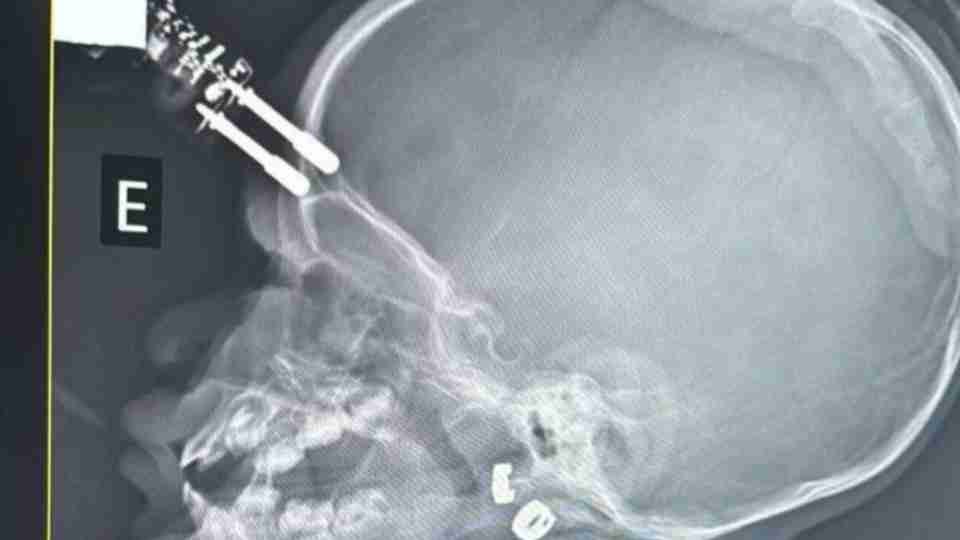

Exames de imagem revelaram que o objeto perfurou o crânio, o que levou a equipe médica a encaminhar a menina imediatamente para o centro cirúrgico. O procedimento teve como objetivo a retirada segura do corpo estranho e a prevenção de possíveis complicações neurológicas.

Um bebê de 1 ano e 4 meses passou por uma cirurgia de urgência após sofrer um grave acidente doméstico em Divinópolis, no Centro-Oeste de Minas Gerais. A criança caiu da cama e acabou ficando com o pino de um carregador cravado na testa. O caso ocorreu na última terça-feira (13).